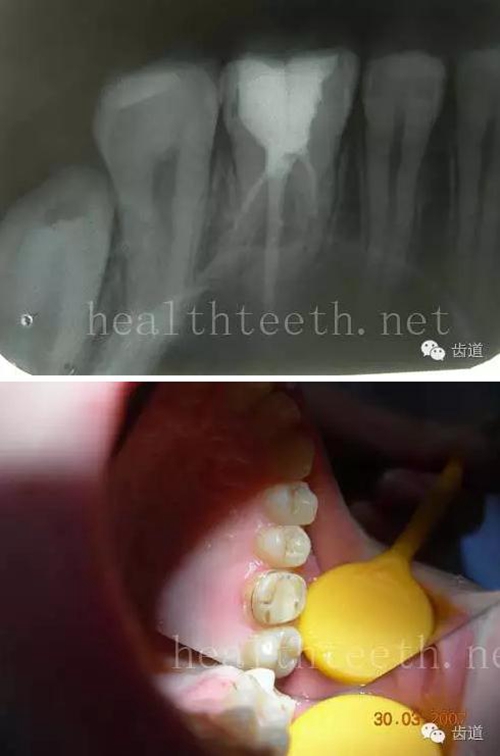

八、牙髓炎、根尖周炎

下面圖片都是慢性根尖周炎的病例,有了齲齒,進(jìn)一步發(fā)展就是牙髓炎,如果此時(shí)沒有得到及時(shí)的治療,疾病會(huì)逐漸發(fā)展破壞到根尖的骨質(zhì),將骨質(zhì)破壞后就在牙齦上出現(xiàn)一個(gè)膿瘺,此時(shí)患者不再感覺到牙齒的疼痛了,往往忽視了治療,但是這種不痛并不是疾病好轉(zhuǎn)了,而是因?yàn)榧膊〉难仔詽B出得到了引流,這個(gè)膿瘺會(huì)出現(xiàn)有時(shí)候變大了,有時(shí)候又變小了,但是如果不治療是不會(huì)自己愈合的,只有經(jīng)過完善的根管治療后才有好轉(zhuǎn)的可能,但是在疾病的治療中時(shí)間是起決定作用的,時(shí)間拖得越晚,好轉(zhuǎn)的可能性越小,經(jīng)過根管治療后如果膿瘺還是沒有消失,就需要做根尖刮治術(shù),如果仍然沒有好轉(zhuǎn),就只能做根尖切除術(shù)了,這對(duì)牙齒的穩(wěn)固是不利的。下面圖片中在膿瘺中插入了一個(gè)牙膠尖,是我們做根管充填用的材料,是非常軟的,就是在口腔牙齦瘺管的地方插進(jìn)去,通過拍牙片可以清晰地看到它到達(dá)的位置,從而確定發(fā)病的牙齒,此處是為了讓大家看得更清楚。

烤瓷牙修復(fù)后牙齦出現(xiàn)兩個(gè)膿瘺,插入牙膠尖,牙片顯示牙膠尖到達(dá)的位置就是根尖炎癥的位置,根尖骨質(zhì)密度降低(發(fā)黑的地方)

牙齒根尖膿瘺,治療前、中、后的圖片對(duì)照,完善根管治療后膿瘺明顯消失了